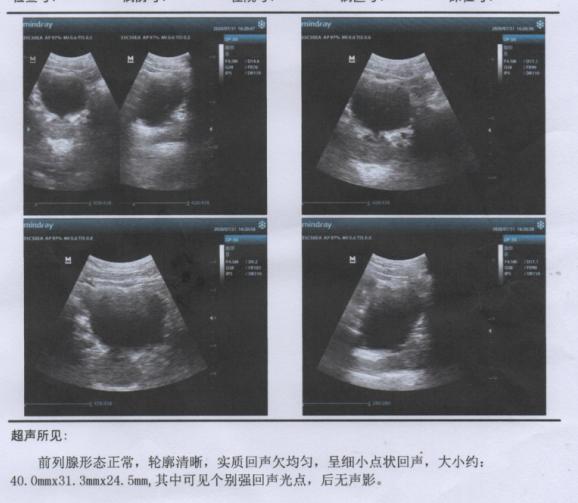

B超:前列腺形态正常,轮廓清晰,实质回声欠均匀,呈细小点状回声,大小约:40.0mm*31.3mm*24.5mm,其中可见个别强回声光点,后未见声影。